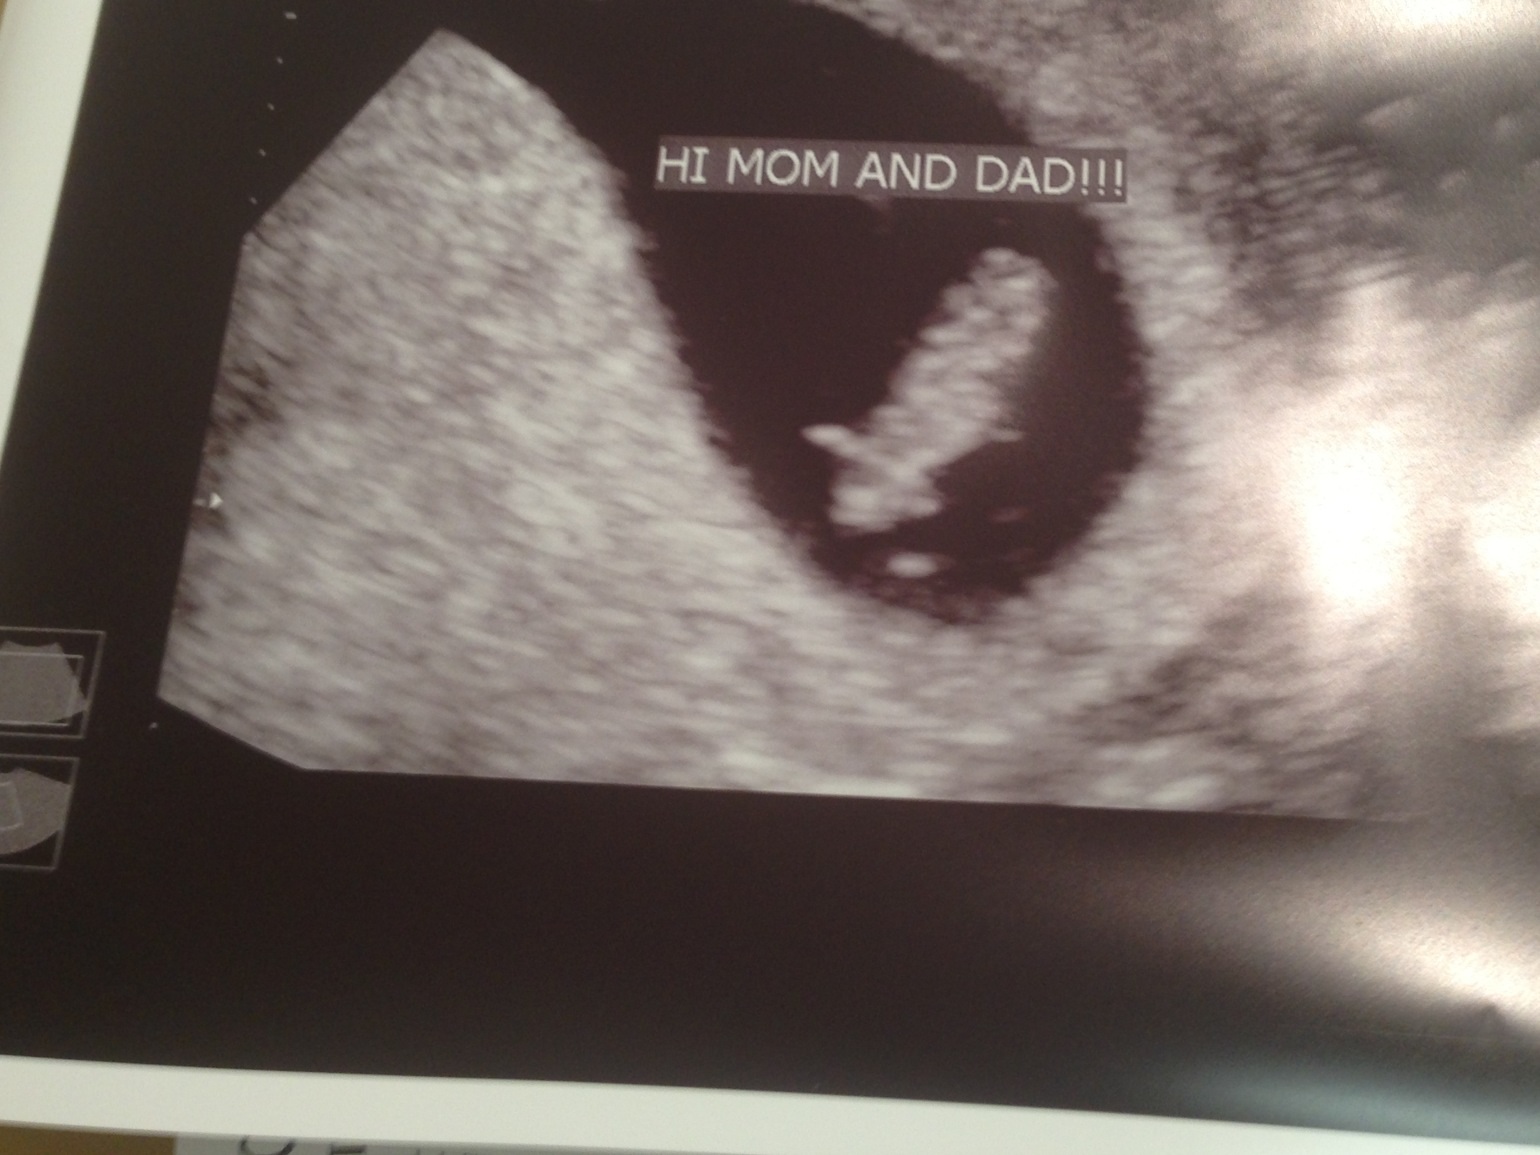

First u/s! Happy pGal mama! PIP

Baby was measuring right on track with a heartbeat of 150bpm. I was so nervous going in but am thrilled to finally feel like I can get excited about this one!! Yay!

• Great news! Am I right that you can see eyes on the pic on the right? :)

• LoL, I thought so too but it is actually brain! But you can see little legs forming.